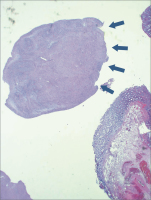

Abbildung 6: Makroschnitt OP-Präparat 12/2012

Histologie

Makroschnitt

Onkologie

Präparat

SMT

submukosaler Tumor